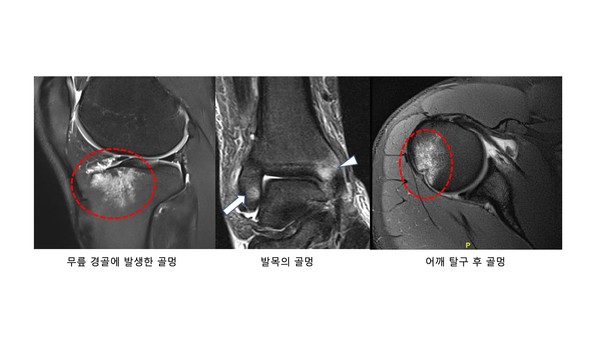

골멍(bone bruise)은 뼈에 발생한 타박상입니다. 타박상이기 때문에 X-레이검사상에서는 정상 소견이지만 MRI소견에서는 뼈 안에 부종 및 멍을 확인할 수 있습니다.

과거보다 현재 이 부상이 각광받는 이유는 아무래도 진단 기술 및 장비의 발달로 볼 수 있습니다. MRI가 대중화되어 있기 때문에 촬영 즉시 확인 가능합니다.

사진에서 보시는 것처럼 골멍이 잘 발생하는 부위는 관절 주위입니다. 뼈의 특성상 관절이 아닌 팔다리의 중간의 뼈는 피질골이라고 하여 쇠파이프처럼 주위가 아주 단단한 무기질로 둘러 쌓여있어 외부에 대한 충격을 모두 막아줍니다. 그러나 관절주위 뼈는 피를 생성하는 골수(bone marrow)가 위치하기 때문에 상대적으로 부드러운 해면골로 구성되어 있습니다. 이 부분은 피질골이 없기 때문에 관절에 대한 충격은 관절연골이 흡수해 주고 있습니다.

정상적인 외력 이상이 발생하게 되는 경우, 즉 연골이 흡수하기 못하는 크기의 외력이 발생하게 되면 해면골에 충격이 가게 되는데 이러한 경우 골멍 (bone bruise)가 발생하게 됩니다.

해면골은 스폰지와 같은 구조이기 때문에 골절 전단계에 골멍이 발생한다고 생각하면 됩니다. 이보다 더 심한 외력이 발생하게 되면 뼈가 삶은 고구마나 감자처럼 으깨지면서 관절이 내려 앉는 골절이 발생할 수도 있습니다.(우리가 알고 있는 뼈가 부숴지고 깨지는 골절은 피질골에서 발생하는 형태입니다.)

첫번째는 해면골 부위에 직접적인 가격입니다. 특히 무릎 부위가 많은데 돌파과정 또는 몸싸움 과정에서 무릎끼리 충돌하는 경우가 많기 때문입니다.

두번째는 충격을 흡수해주는 연골의 손상이 있는 부위에 외력이 발생한 경우입니다. 농구라는 종목이 무릎에 부담이 많이 가는 스포츠 이기 때문에 무릎 연골의 손상을 이미 가지고 있는 선수들이 많습니다. 따라서 상대와의 충돌이 아니더라도, 손상받은 연골 부위는 뼈를 보호하는 역할을 하는 구조가 없기 때문에 직접적으로 모든 충격이 뼈로 전달될 수 있어 골멍에 취약합니다.

세번째는 어깨 탈구나 십자인대 손상처럼 관절의 탈구가 일어나 뼈가 어긋나면서 발생하게 되는 비정상적인 뼈의 충돌입니다. 관절 주위 뼈에 안정성을 부여해주는 인대가 손상이 되면 순간적으로 뼈의 위치관계가 어긋나게 됩니다. 그렇게 되면 비정상적인 충돌이 발생하면서 다시 본래의 자리를 찾아가게 되는데요, 이 충돌과정에서 뼈에 타박상, 즉 골멍이 발생할 수 있습니다.